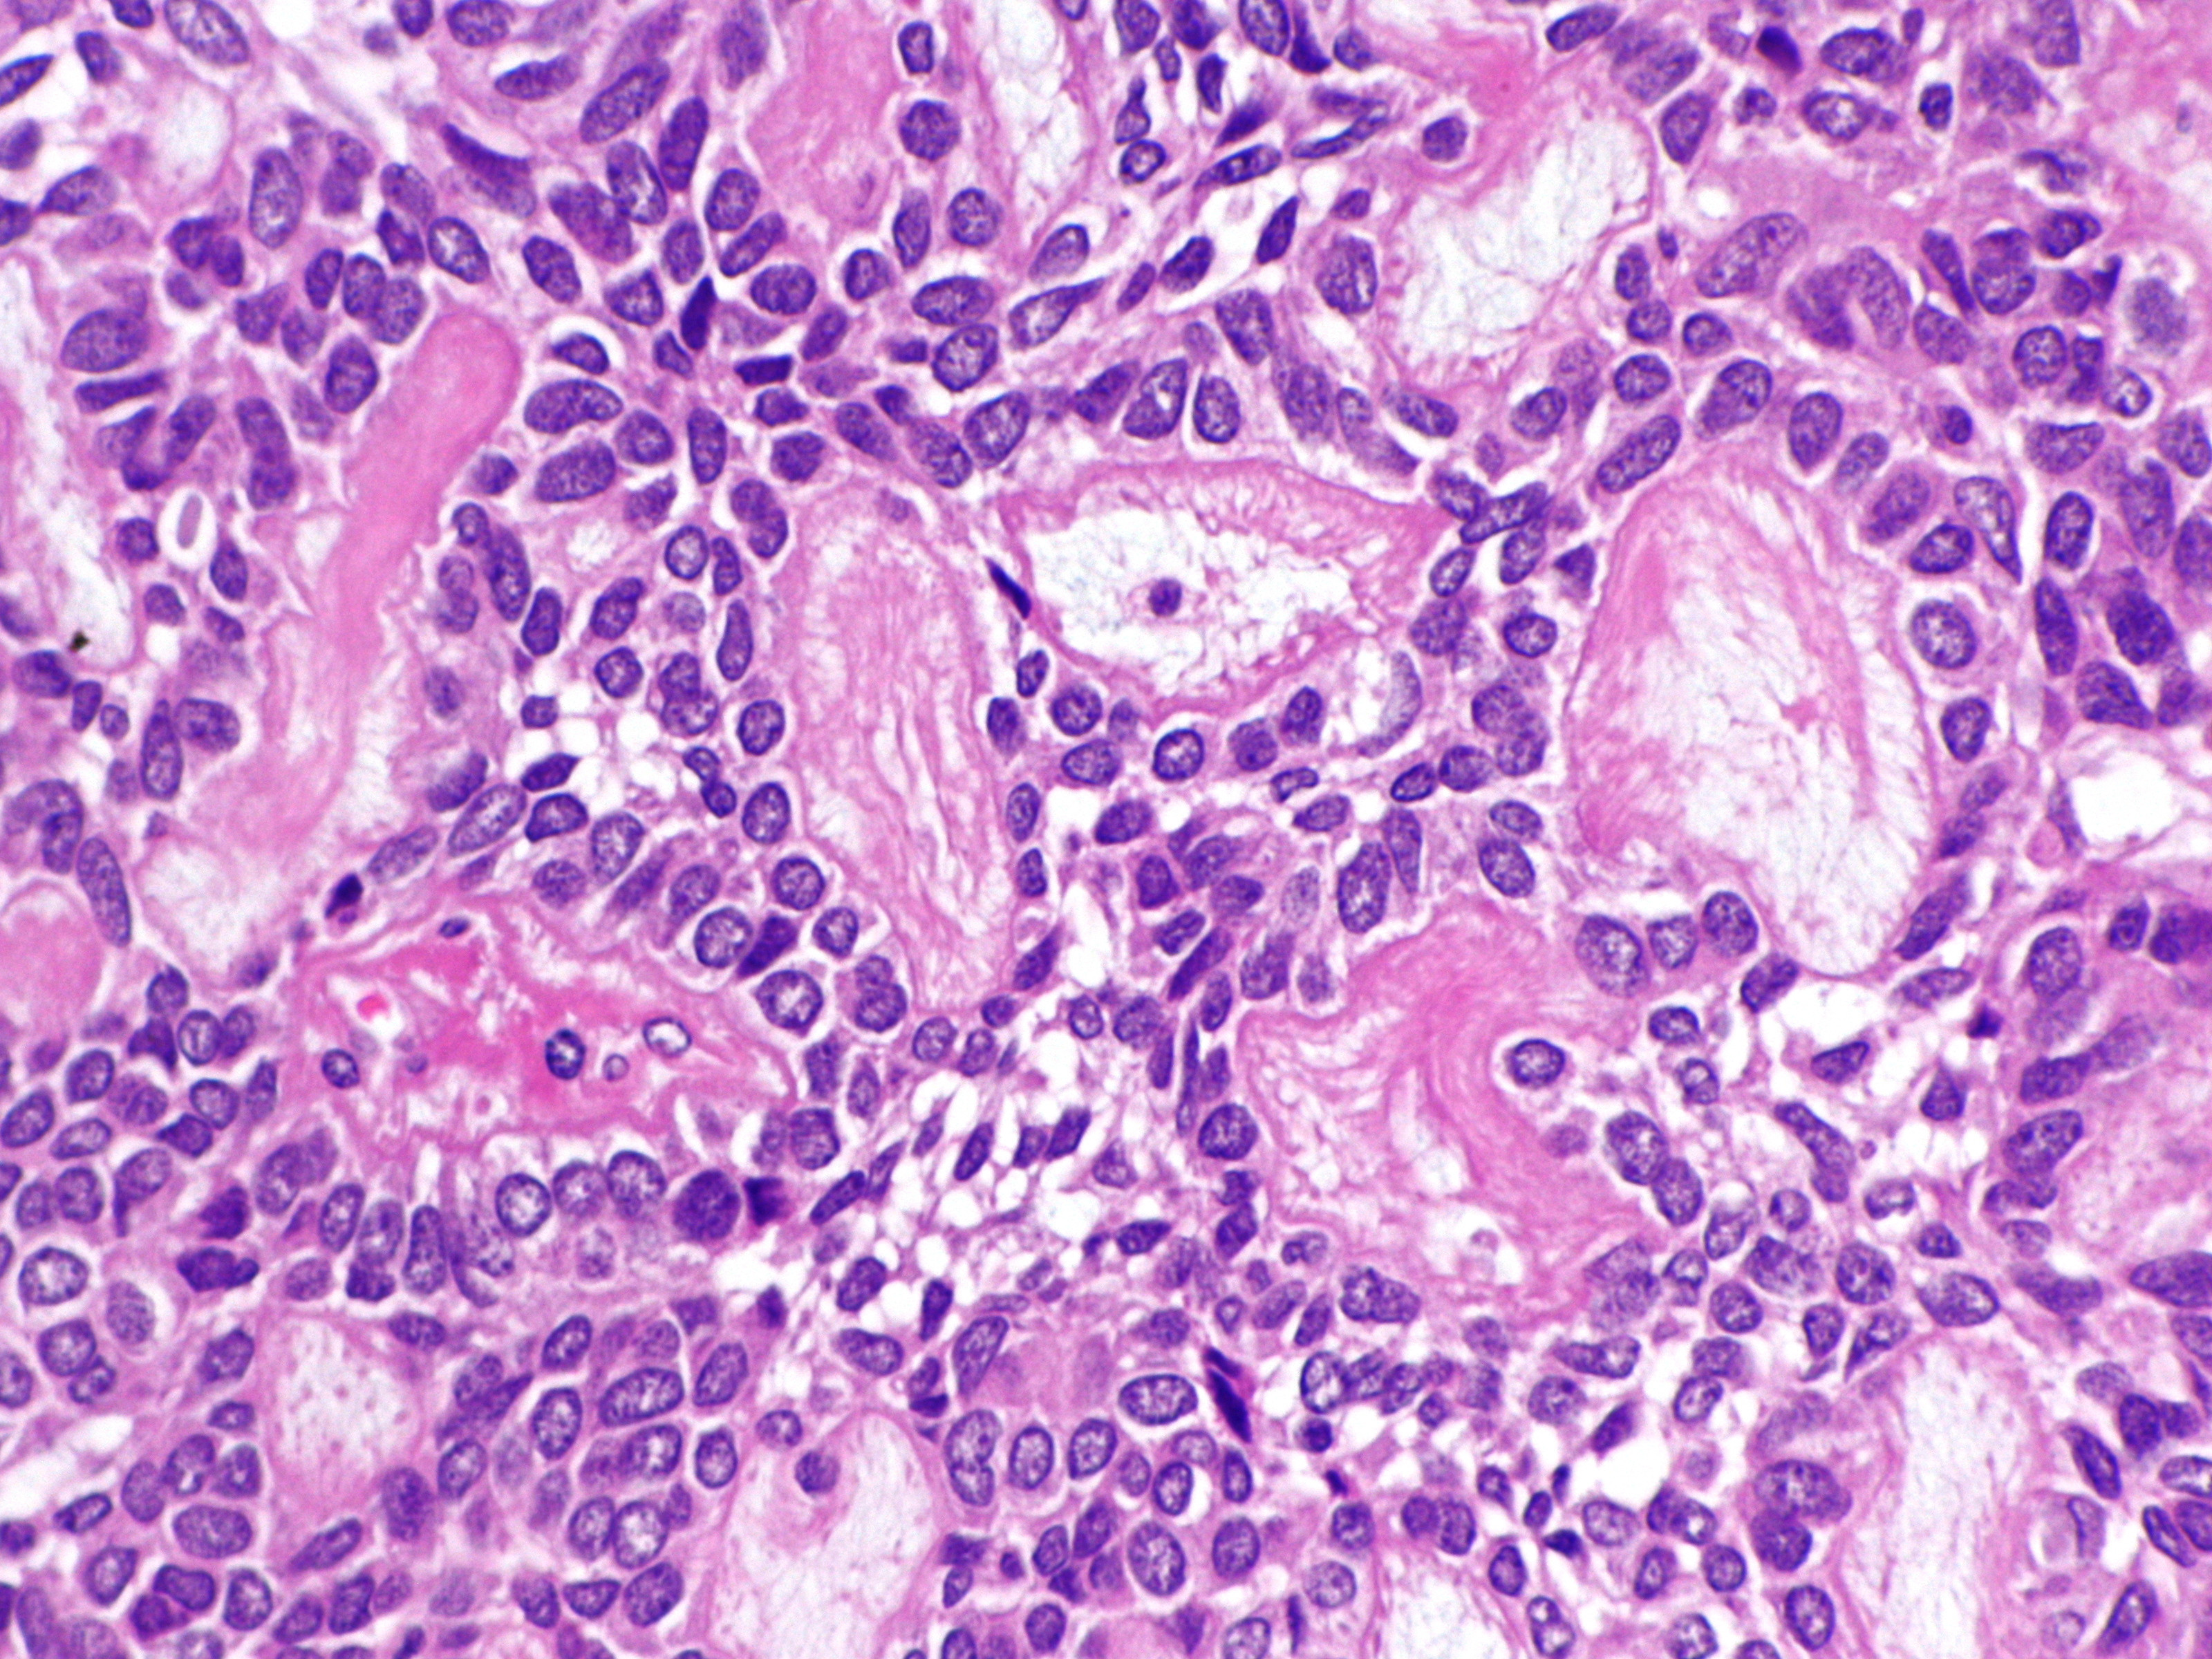

PA nodulair basaalcelcarcinoom:

Verbonden met de epidermis of de haarfollikels, soms schijnbaar zelfstandig

zonder duidelijke relatie hiermee, ziet men epitheel eilanden gekenmerkt door

donkere cellen met relatief weinig cytoplasma. De celgrenzen zijn soms niet

duidelijk en het geheel lijkt te bestaan uit een massa van donkere celkernen,

elk met een smal licht protoplasmarandje en omgeven door een rand van kernen

van hetzelfde type die als palissaden naast elkaar staan op dezelfde wijze als

in het stratum basale en rond de haarpapil. Er zijn geen celbrugjes te zien

zoals in het stratum spinosum; de door de palissadelaag ingesloten kernen lijken

wat ongeordend bij elkaar te liggen. De kernen hebben een regelmatig, uniform

aspect, ze bezitten geen anaplastische kenmerken en tonen geen abnormale mitosen.

Meestal zijn er hoorncysten in het epitheel; er is een directe overgang van

'basaloide' cellen in hoorn en niet, zoals in de epidermis, via voorstadia zoals

stratum spinosum of stratum granulosum. Deze hoorncysten komen voor bij vrijwel

alle vormen en varianten van het carcinoma basocellulare, soms echter vormen

ze een hoofdkenmerk. Het bindweefsel in de cutis blijkt in relatie tot de tumorcellen

mee te groeien, er is geen infiltratieve groei. Dit blijkt o.a. uit het feit

dat zich bij de fixatie vaak spleten vormen op de grens van carcinoom-bindweefsel,

een verschijnsel dat niet bij carcinoma spinocellulare (waarbij wel infiltrerende

groei plaatsvindt) te zien is. Het bindweefsel rond de tumorveldjes bevat vele

jonge fibroblasten en is hier bovendien metachromatisch (zure mucopolysacchariden)

en PAS-positief als bij de haarpapillen. De vaten zijn toegenomen en verwijd;

er is soms opvallend weinig cellulair infiltraat. Soms echter bevindt zich,

vooral vlak bij de tumorveldjes, enig lymfocytair infiltraat. Is ulceratie opgetreden

dan neemt het infiltraat toe en bevat het aan de oppervlakte soms talrijke polynucleaire

granulocyten. Carcinoma basocellulare komt niet aan de slijmvliezen voor. Zie